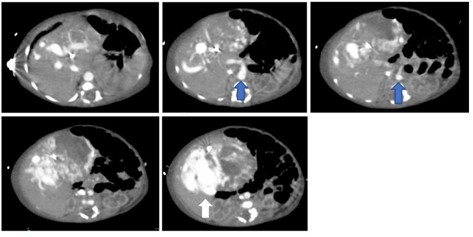

Metástasis

Las metástasis son el tumor hepático maligno más frecuente y ocurren hasta 18 veces más que los tumores primarios. Como consecuencia de la circulación portal el hígado es el órgano en el que más frecuentemente se localizan metástasis. Entre el 60% y el 80% de los pacientes con antecedentes de carcinoma colorrectal, carcinoma de páncreas, cáncer de mama y otros tumores como los neuroendocrinos desarrollan metástasis hepáticas. La supervivencia de los pacientes con metástasis hepáticas depende de su extirpación quirúrgica.

La evidencia de las lesiones hepáticas obedece tanto al número y localización dentro del hígado, como a la presencia o no de enfermedad extrahepática. Esto último es importante en el proceso de selección de aquellos pacientes a los que se les debe o no ordenar una cirugía hepática. En la tomografía sin contraste las metástasis suelen ser iso o hipodensas respecto del resto de parénquima, salvo en casos de sangrado o calcificación intralesional en que pueden ser hiperdensas. Podemos observar calcificaciones en metástasis de tumores mucinosos del tracto gastrointestinal o en metástasis de ovario, mama, pulmón, riñón y tiroides.(18) Las metástasis suelen tener el mismo comportamiento que el tumor de origen, suelen ser hipovasculares en tumores de colon, pulmón, adenocarcinoma de páncreas y en tumores de vejiga y próstata. Se observan lesiones hipervasculares en tumores primarios de tiroides, tumores neuroendócrinos (carcinoide, tumor de islotes pancreáticos, feocromocitoma) y en melanoma, cáncer renal, coriocarcinoma y sarcomas.(18-19)

Dentro de los patrones de reforzamiento de las metástasis lo más frecuente que podemos encontrar en fase arterial es la captación periférica y continua (por efecto de parasitación de la lesión y reacción desmoplástica/inflamatoria del parénquima adyacente), metástasis homogéneamente hipercaptantes (suelen ser menores de 1,5 cm), metástasis heterogéneas por fibrosis y necrosis central (> 3 cm) o con mínima captación periférica (lesiones hipovasculares).(18) En las fases portal y venosa tardía el patrón más frecuente es la captación progresiva incompleta. En menor grado se observan lesiones que se hacen isodensas con el resto de parénquima o persistencia de una mínima captación periférica (Anexo 17). El fenómeno de lavado (washout) periférico se ha descrito como hallazgo típico de metástasis, consiste en la desaparición del contraste en la periferia de la lesión en fases retardadas, es más frecuente en las metástasis hipervasculares, especialmente en tumores neuroendocrinos. Supone una mejor vascularización arterial y venosa en la periferia, donde se sitúa el tumor viable, respecto al centro de fibrosis o necrosis.(18-22)

Dentro de las lesiones malignas que se describen en el siguiente gráfico, los hepatocarcinomas (Anexo 34) son los que encabezan la lista de las más halladas, representando el 3% (correspondiente a 16 pacientes, 14 de sexo masculino y 2 de sexo femenino). Les siguen los colangiocarcinomas (Anexo 35), que equivalen al 3% de la muestra (13 pacientes, 10 de sexo masculino y 3 de sexo femenino), siendo esta lesión encontrada en pacientes con decendencia asiática mayoritariamente. Continúan los hepatocarcinomas fibromelar, con el 2% (10 pacientes, 8 de sexo masculino y 2 de sexo femenino), evidenciados más en pacientes jóvenes entre los 18 y 30 años (Anexo 36), y metástasis (Anexo 37), representan un bajo porcentaje dentro de la población estudiada, siendo estos últimos eel 1% de la población (6 pacientes, 5 de sexo masculino y 1 de sexo femenino); dicha metástasis en la paciente fue hipervascular, desencadenada a raíz de un tumor pancreático (Anexo 38).